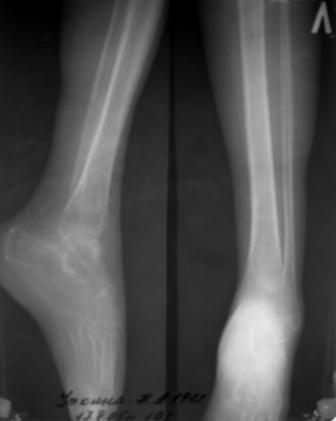

Стопа

Стопа 2

Получила травму в феврале 2004г в г.Лобытнанги ЯНАО Тюм.обл. Через неделю после поступления выполнен остеосинтез лонного сочленения пластиной. 1,5 месяца на скелетном вытяжении. В последующем ходит при помощи костылей с нагрузкой на правую ногу. Имеется нестабильность половин таза, неправильно-консолидированный перелом левой вертлужной впадины, невропатия седалищного нерва слева. В результате невропатии седалищного нерва сформировалась эквинусная установка левой стопы, парестезии по подошвенной поверхности.

Направлена к нам для устранения патологической установки стопы и эндопротезирования левого тазобедренного сустава, также имеется миграция шурупов пластины, фиксирующей лонное сочленение.

Клинически: ходит на костылях с нагрузкой на правую ногу. Левая стопа в эквинусе. Осевая нагрузка на левую н\конечность болезненна в области левого тазобедренного сустава, при прикосновениях к подошвенной поверхности стопы у пациентки чувство зжения. В левом коленном суставе полный обьем движений, в левом тазобедренном резко ограничено отведение и ротация, укорочение левой н\конечности на 2,5 см. При полипроекционной и функциональной Р-графии выявлена нестабильность левого КПС и лонного сочленения, консолидированный в порочном положении поперечный оскольчатый перелом левой вертлужной впадины с центральным смещением головки бедра. Нами выполнена коррекция деформации левой стопы. Планируется выполнить введение 2 канюлированных илиосакральных винтов слева, реостеосинтез лонного сочленения реконструктивной пластиной, после заживления ран - тотальное эндопротезирование левого тазобедренного сустава.